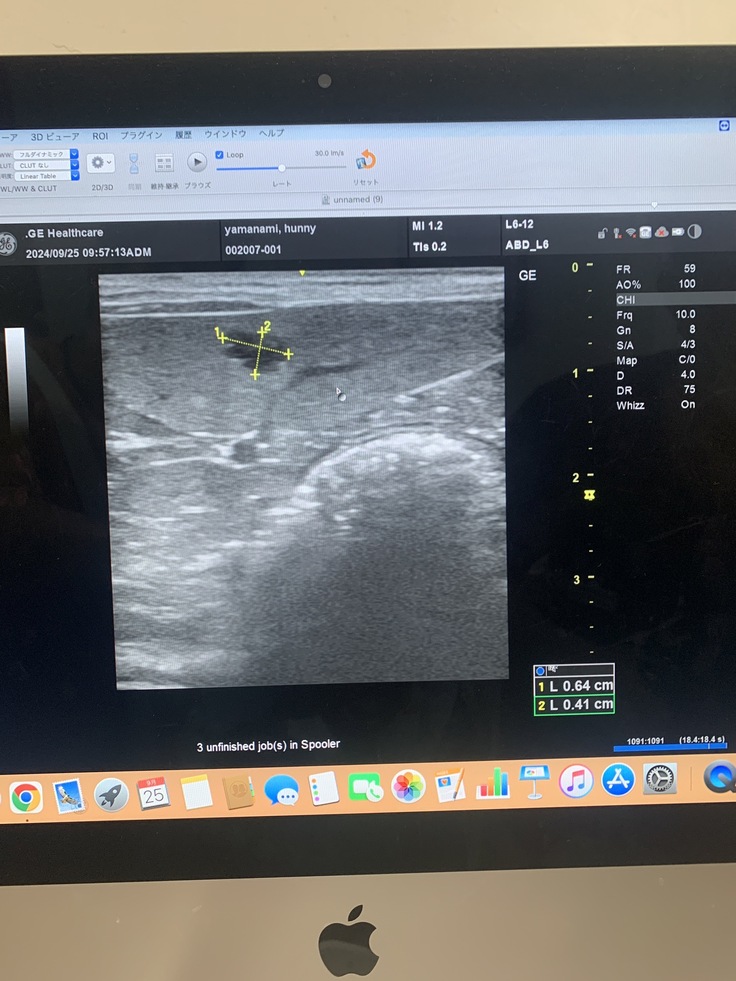

9月25日かかりつけ受診と脾臓の転移見つかる

脾臓にしこり、影→1センチ4ヶ所が見つかった